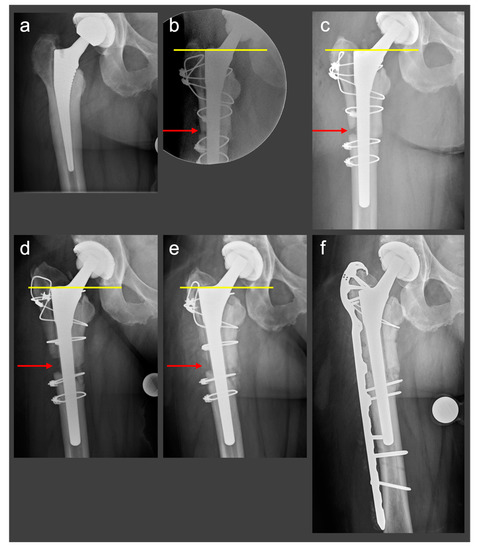

2.2.2. Clinical Case

2.3. Novel Surgical Technique: A Monocortical Screw for Preventing Trochanteric Escape

2.3.1. The Surgical Technique

2.3.2. Biomechanical Principles

2.3.3. Clinical Case